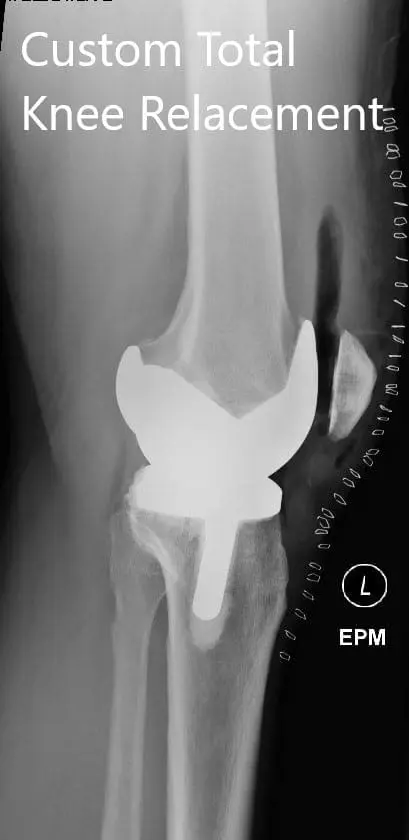

Postoperative X-ray showing the lateral view of the right and the left knee

Postoperative X-ray showing the lateral view of the right and the left knee - img 2